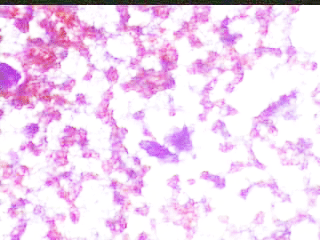

Το ελάχιστο υλικό, επιστρώνεται  σε αντικειμενοφόρο  πλάκα, στεγνώνει στον αέρα και  βάφεται κατά Papanicolaou . Δείγμα  από τις  κυτταρολογικές  εικόνες

Ανάμεσα σε άφθονα ερυθρά αιμοσφαίρια, ατυπα αδενικά κύτταρα, με διογκωμένους, ανισομεγέθεις πυρήνες, με διαταραχή της χρωματίνης. Υπόνοια για τοπική υποτροπή αδενοκαρκινώματος μαστού .